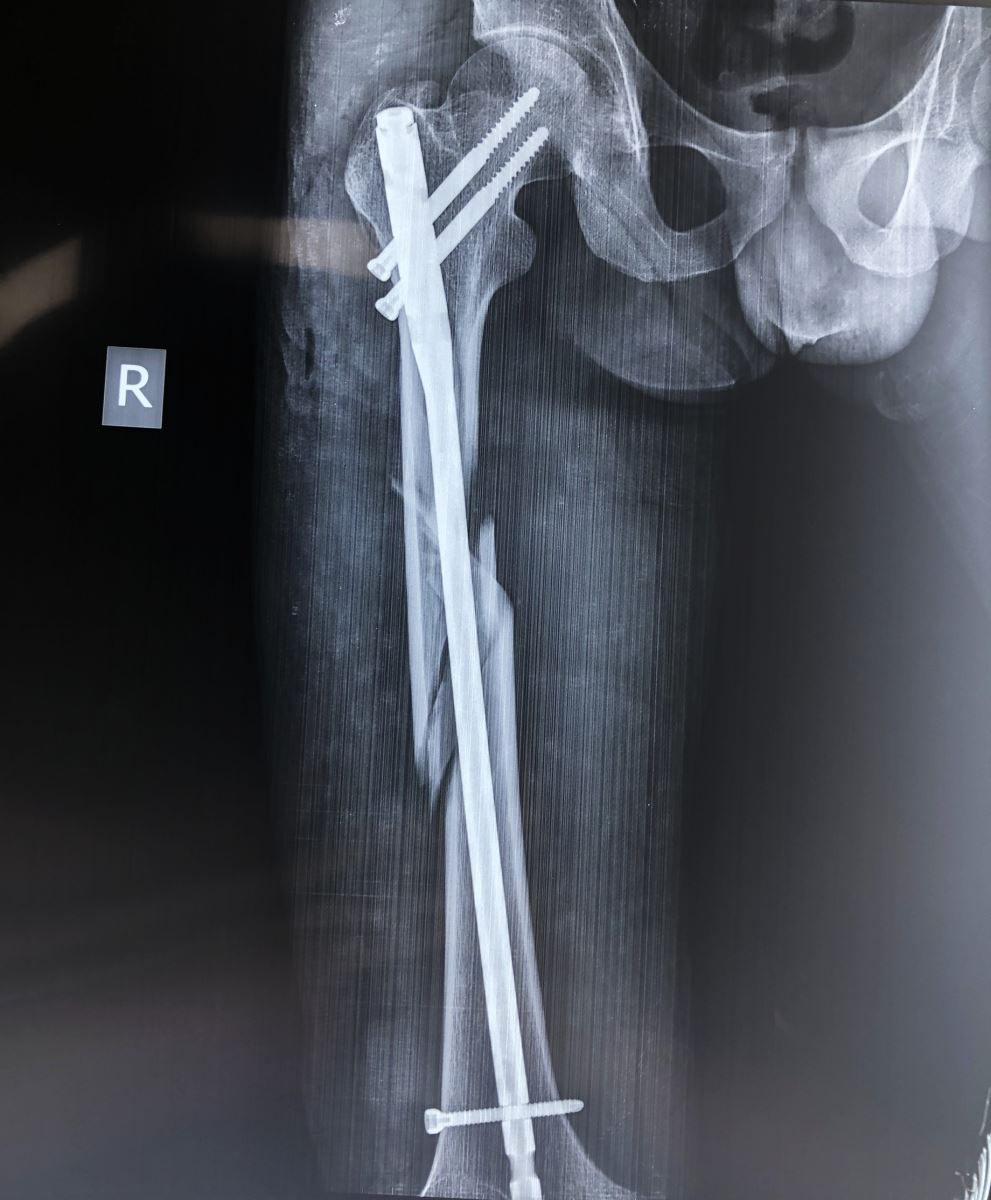

Là phương pháp điều trị hữu hiệu tích cực nhất hiện nay.

Đóng đinh nội tủy:

Áp dụng cho các trường hợp gãy thân xương đùi, tốt nhất đoạn 2/4 giữa, áp dụng trong tất cả các trường hợp gãy ngang, chéo, nhiều mảnh, gãy 2 ổ. Đóng đinh nội tủy được xem là phương pháp tốt nhất hiện nay. Nhờ màn tăng sáng, người ta đóng đinh không mở ổ gãy và có khoan rộng ống tủy. Để chống xoay của đoạn gãy xa người ta tăng cường chốt ngang qua xương. Trong trường hợp đường gãy thấp ở đoạn 1/3 giữa và dưới, có thể tiến hành đóng đinh nội tủy có chốt ngang ngược dòng từ đầu dưới xương đùi.